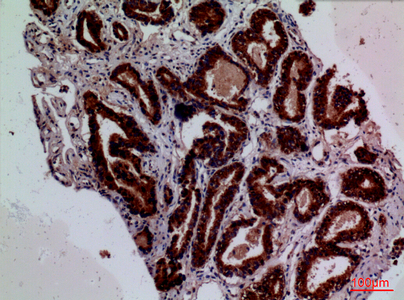

Anti-F3 Antibody

- Product NameAnti-F3 Antibody

- Scientific DescriptionRabbit polyclonal antibody to F3.